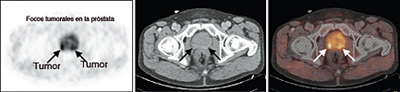

El estudio de los huesos mediante gammagrafía ósea debe ser efectuado si hay sospecha de lesiones óseas y/o el PSA es superior a 10 ng/ml. En ocasiones se realiza un PET-TC con colina para evaluar la presencia de metástasis.